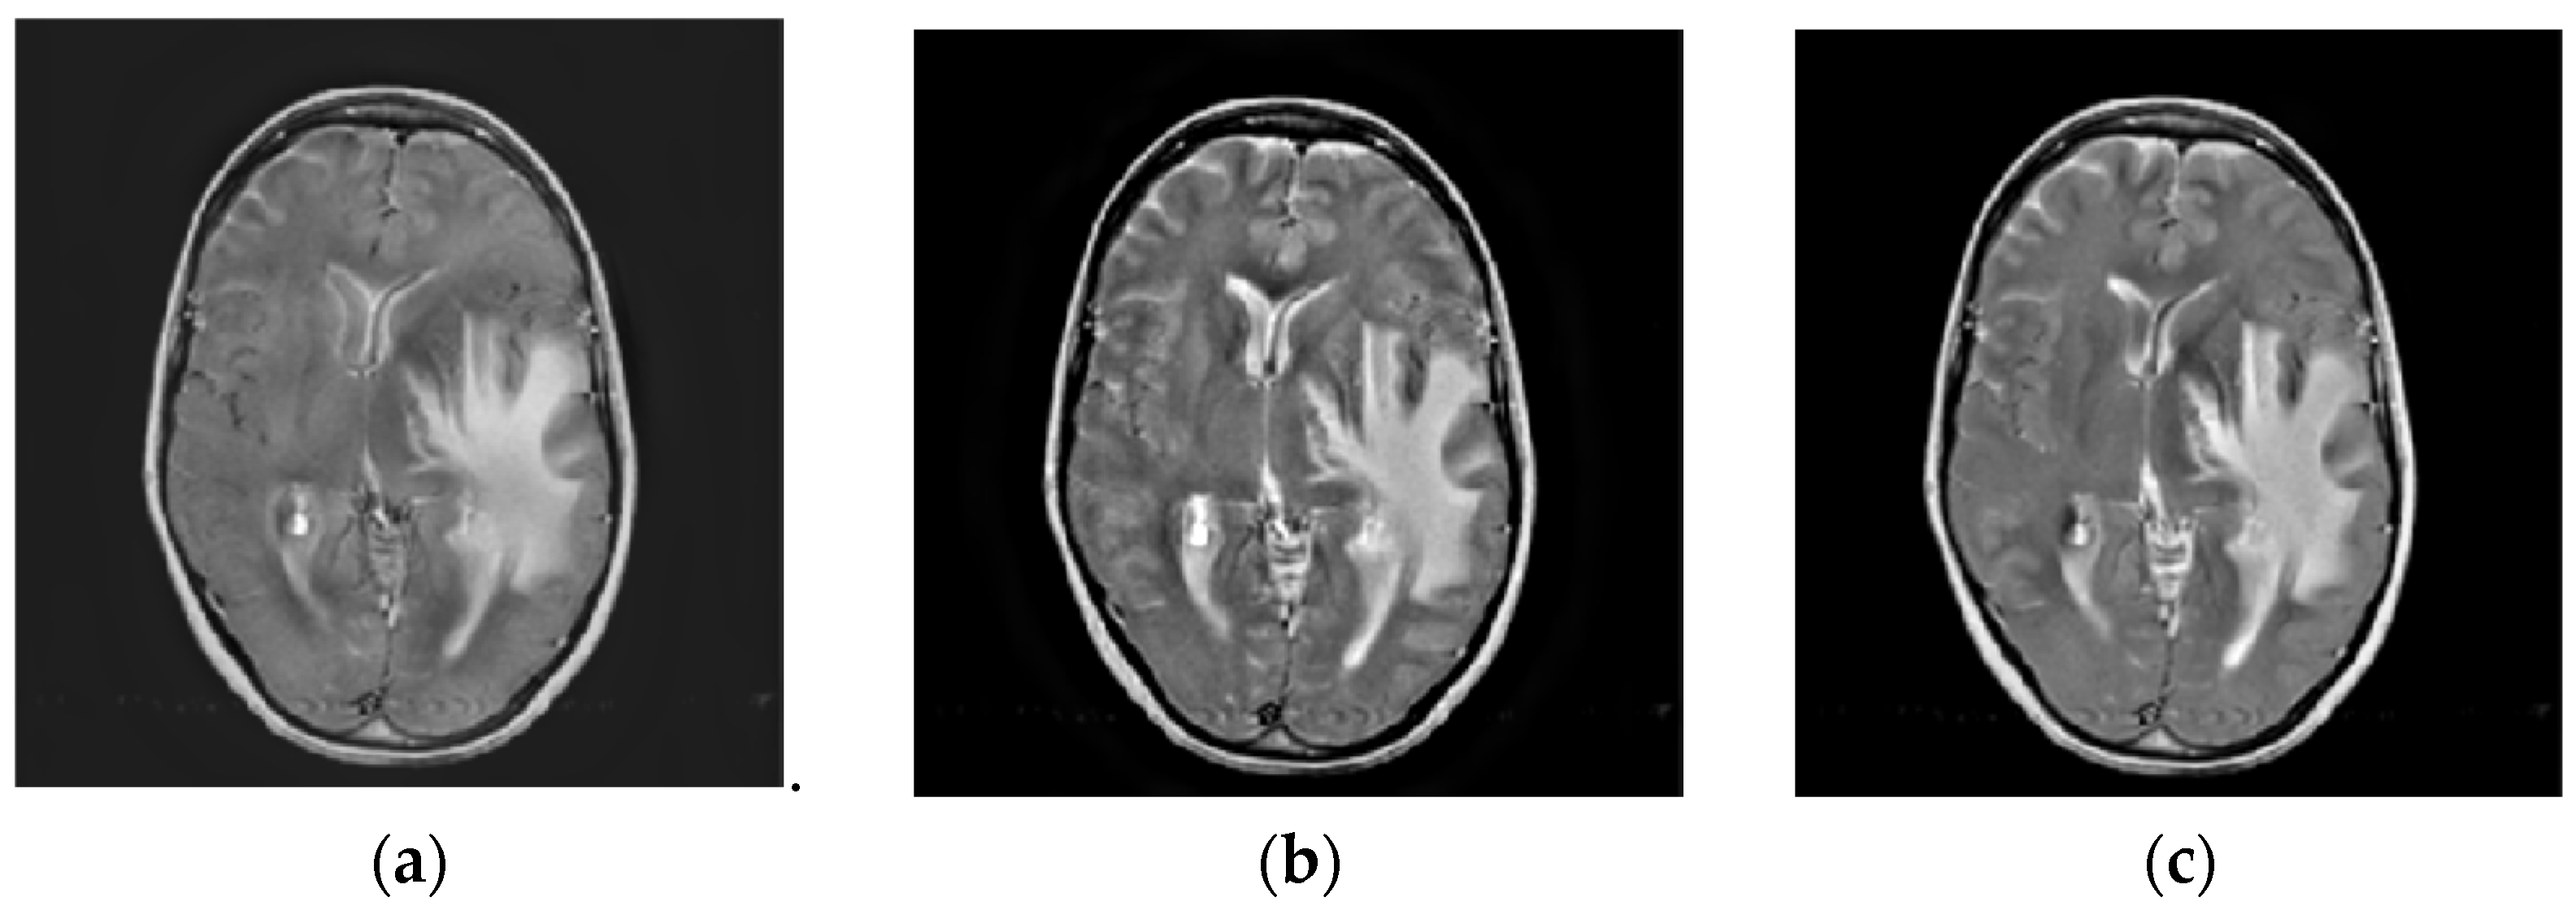

4.2. Comparison of Gray Image Fusion